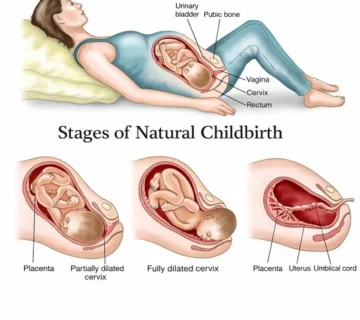

تمارين كيجل (Kegel)

مع ازدياد وزن الرحم، تضغط على عضلات قاع الحوض التي تدعم المثانة والرحم.

تمارين كيجل تقوّي هذه العضلات وتساعد على الولادة السهلة ومنع السلس البولي.

طريقة التمرين:

-

شدّي عضلات الحوض كما لو كنتِ توقفين تدفق البول.

-

اثبتي ٤ ثوانٍ ثم استرخي.

-

كرّري التمرين ١٠ مرات في كل جلسة، عدة مرات يومياً.

يمكنكِ ممارستها في أي وقت — أثناء القيادة أو الجلوس أو الاسترخاء.